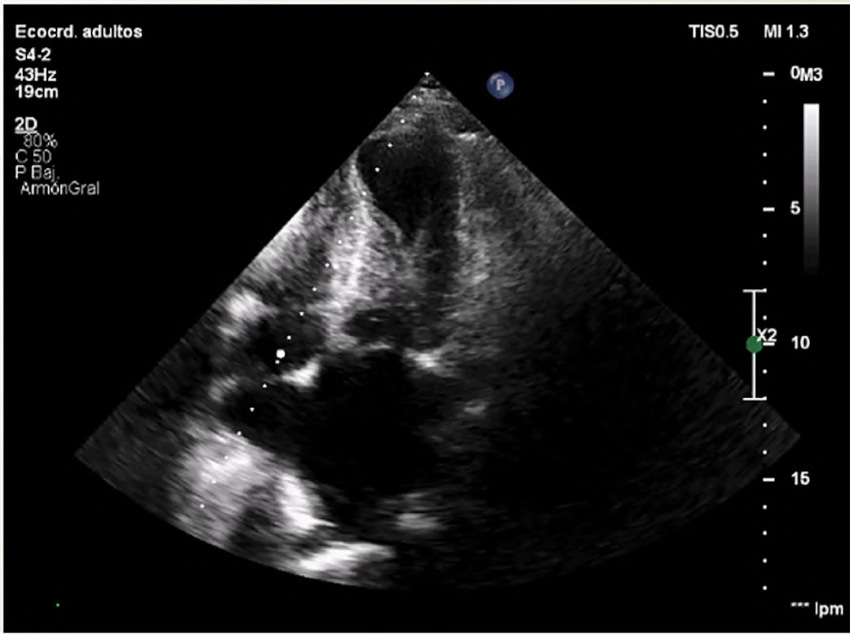

The patient's condition was stable, and she was transferred to the Coronary Care Unit, where a color Doppler echocardiogram was performed, revealing preserved left ventricular dimensions, akinesia of all apical segments, hypercontractility of the basal segments and mild to moderately reduced systolic function, with an estimated left ventricular ejection fraction (LVEF) of 45%. A mid-ventricular gradient of 45 mmHg was observed, and a pulmonary artery systolic pressure of 60 mmHg was estimated (Figure 1).